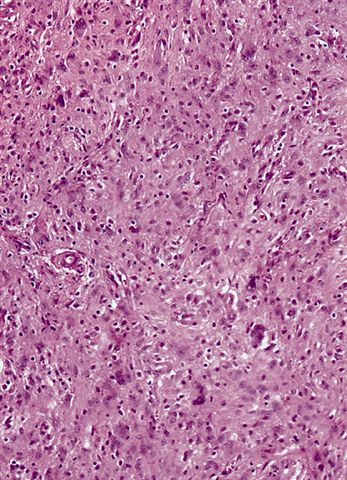

Microscopic (histologic) images

Contributed by Michael Clay, M.D., Melanie Bourgeau, M.D. and AFIP

Morphologic variability:

- Sclerosing subtype

- Second most common subtype

- Predilection for retroperitoneal or paratesticular location

- Collagenous fibrous tissue with scattered adipocytes and atypical multinucleated stromal cells

- Scant lipogenic component may be missed in small samples

- Inflammatory subtype

- Rare

- Almost always in the retroperitoneum where it is confused with nonlipogenic tumors

- Chronic inflammatory cells (B > T cells) with occasional lymphoid follicles scattered in a cellular fibrocollagenous stroma with sparse multinucleated atypical cells

- May obscure adipocytes